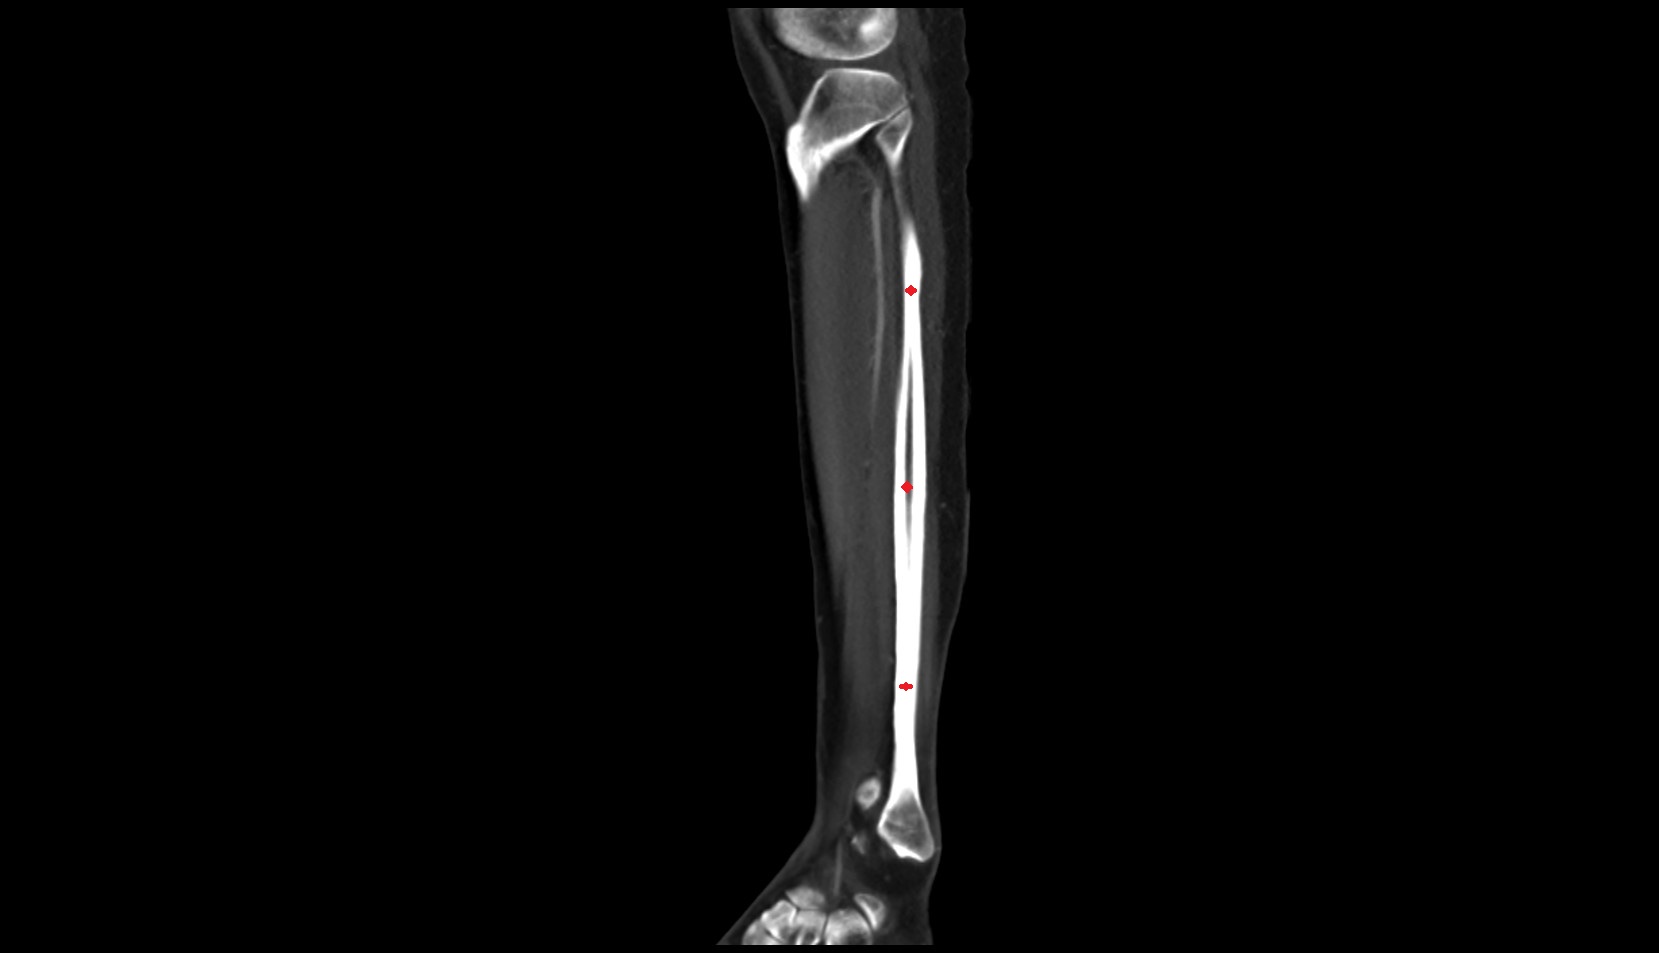

- Body of tibia

- Tibia

- Fibula